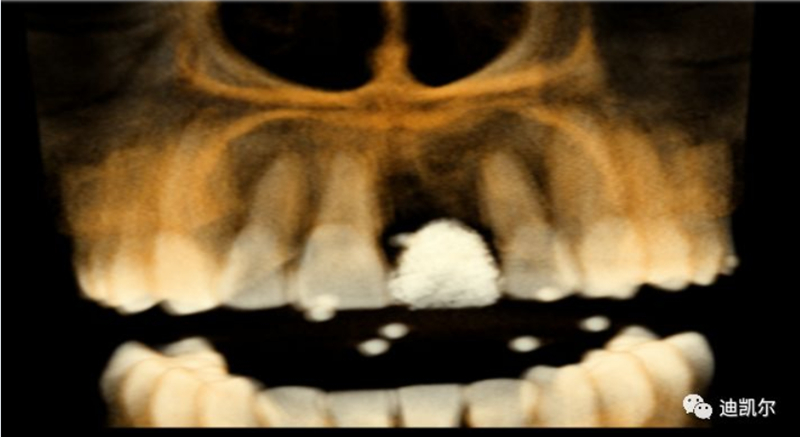

術(shù)前CBCT圖像和測量數(shù)據(jù)

難點分析

*前牙美學區(qū)種植,病人為正畸治療后,對美學要求高

*早期種植病例,頰側(cè)組織凹陷,肉眼可見骨缺損,需要種植同期GBR

*CBCT顯示骨缺損嚴重,種植窩洞制備困難,種植體很難獲得初期穩(wěn)定性

*修復(fù)體設(shè)計為舌側(cè)窩穿出螺絲固位,對種植體位置和長軸要求很高